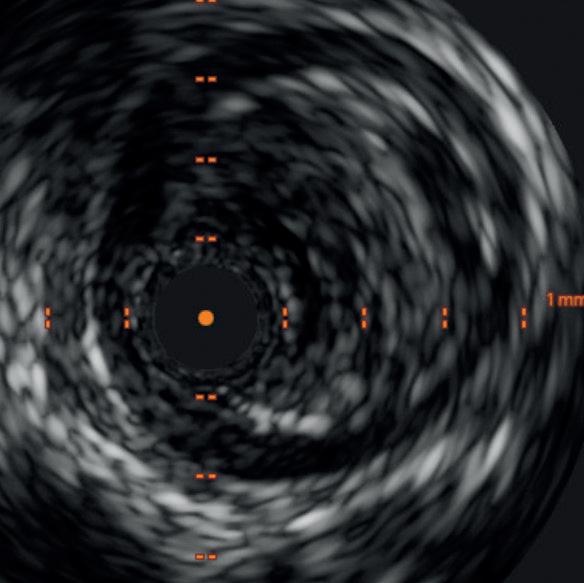

Diagnostic angiogram demonstrated a right popliteal occlusion extending into his proximal tibial vessels (Figure 1). An 0.014” wire was able to easily cross the lesion and pass into the posterior tibial vessel. Intravascular ultrasound (IVUS) demonstrated chronic intraluminal thrombus

with limited evidence of atherosclerosis (Figure 2). A 2.0mm Auryon laser catheter was used to perform a simultaneous athrectomy-thrombectomy (Figure 3). After a single pass, repeat angiogram demonstrated >70% luminal gain (Figure 4). Low pressure (2atm) balloon angioplasty was then performed (Figure 5). Completion angiogram (Figure 6) demonstrated no residual stenosis, with brisk flow into the posterior tibial vessel. The patient developed a palpable posterior tibial pulse, and, at six months, has no claudication symptoms.